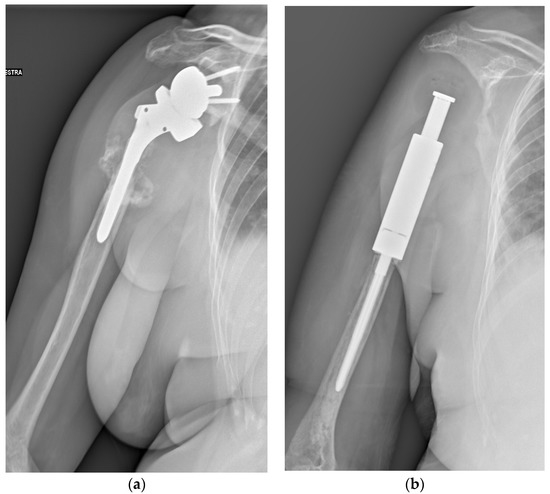

Figure 3.

A 71-year-old female patient underwent en bloc resection and reconstruction with a prosthesis for a bone giant cell tumor of the proximal humerus with a pathological fracture at presentation. Six months postoperatively, she experienced local recurrence and was treated with denosumab for 2 years and 5 months (a). She then underwent tumor resection and revision of prosthesis (b). One year after the revision, she experienced local re-recurrence and underwent tumor resection. One month later, a third local recurrence and lung metastasis were detected, and the biopsy revealed malignant transformation (c). She died of the disease 6 years and 4 months after the first surgery (Case 26, Table 3 and Table 4).